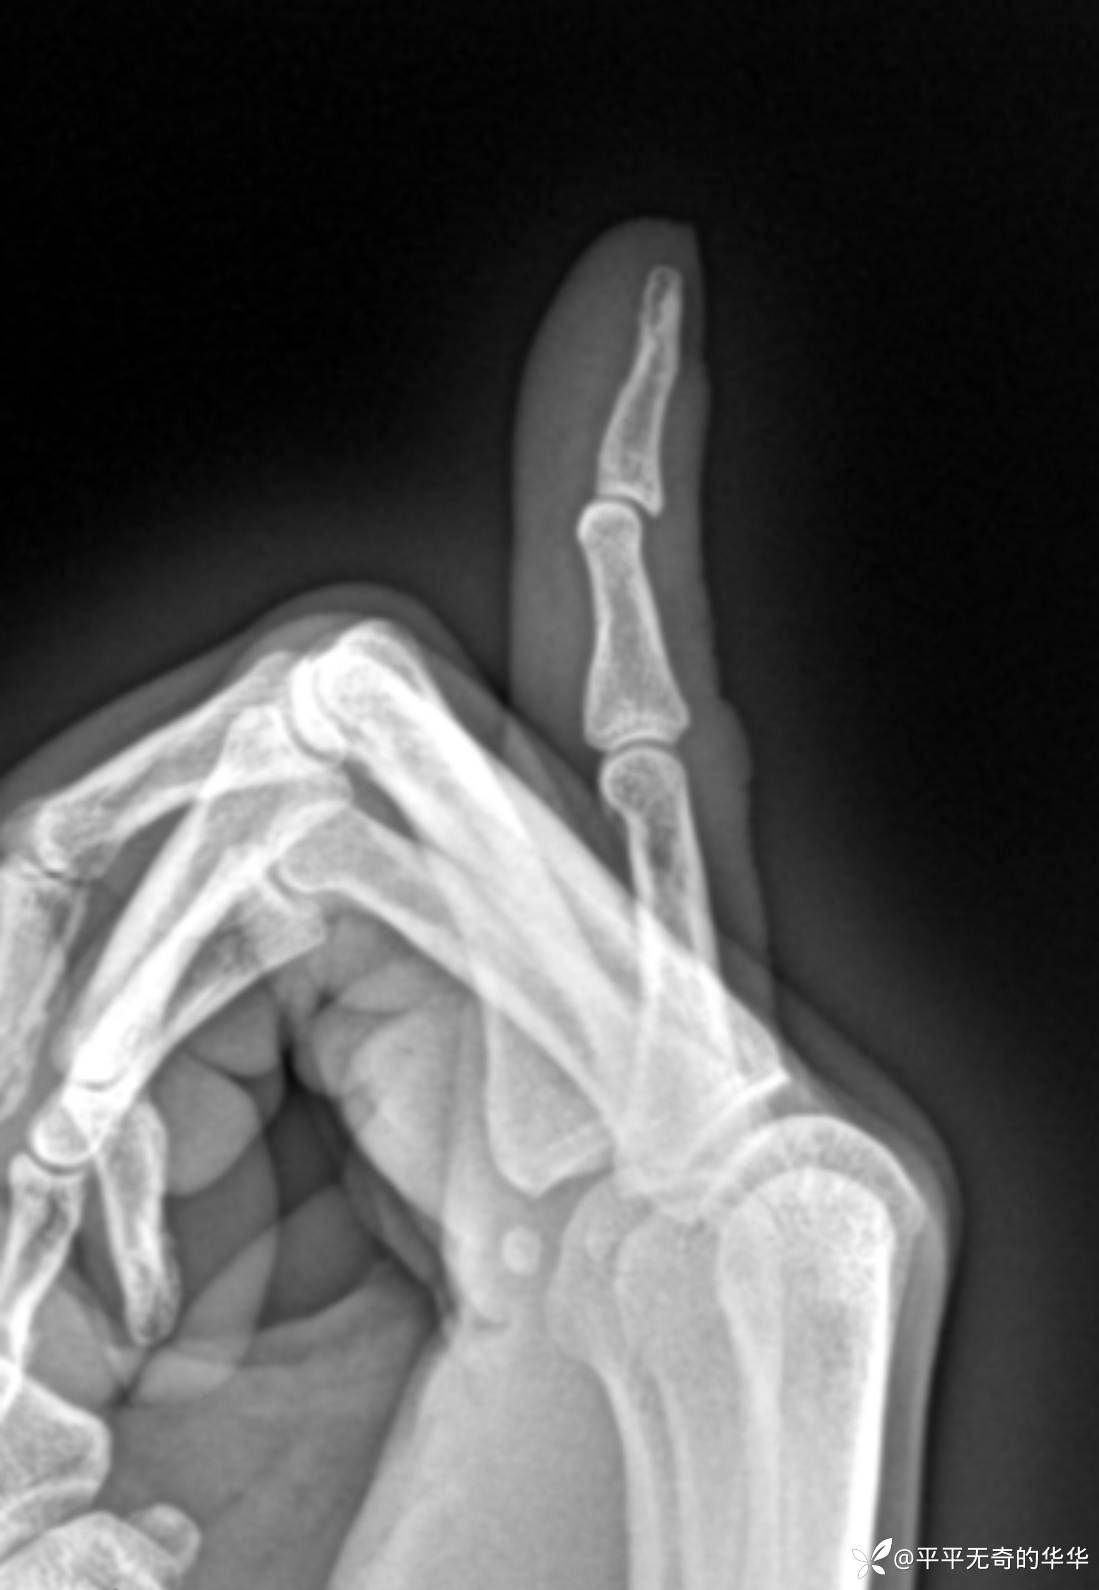

X线侧位可见小指远侧指间关节向背侧半脱位改变